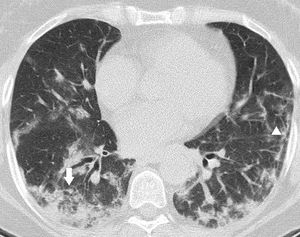

Case reportsPatient 152-year-old white male. His prior medical record was unremarkable. He had a positive RT-PCR for SARS-CoV-2 on the 11th day of symptoms. Prior to admission, he had used azithromycin and amoxicillin-clavulanate. A chest X-ray (CXR) upon admission showed a slight infiltrate on the right lower lobe. On day 1 of hospitalization, he was started on a daily dose of dexamethasone at 6 mg PO. Four days later, continuous positive airway pressure (CPAP) was also started. Throughout the following 10 days (on illness day 21), his P/F ratio on arterial blood gas trended upwards from 85 to 230 despite sustaining dyspnea, fever, leukocytosis, and high titers of C-reactive protein. He then underwent a CT scan, which revealed a pattern compatible with OP (Fig. 1). Soon after being started on prednisone at 1 mg/kg PO, CPAP was stopped, and oxygen support was switched to low-flow nasal cannula. He rapidly experienced significant improvement in both symptoms and laboratory tests. He was finally discharged on day 11 of prednisone use after a full recovery.

Pulmonary CT angiography to assess pulmonary embolism (PE) obtained on illness day 21. CT axial image (lung window) showed peripheral areas of consolidation in both lower lobes. Incipient architectural distortion is seen in central portions of the lungs. CT findings were suggestive of OP. PE was absent.